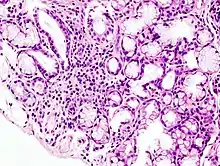

Histopathologic image of focal lymphoid infiltration in the minor salivary gland associated with Sjögren syndrome. Lip biopsy. H & E stain

Sjögren's syndrome is an auto immune disorder where immune cells attack the salivary and tear glands. This can play havoc with oral hygiene and lead to rampant caries.